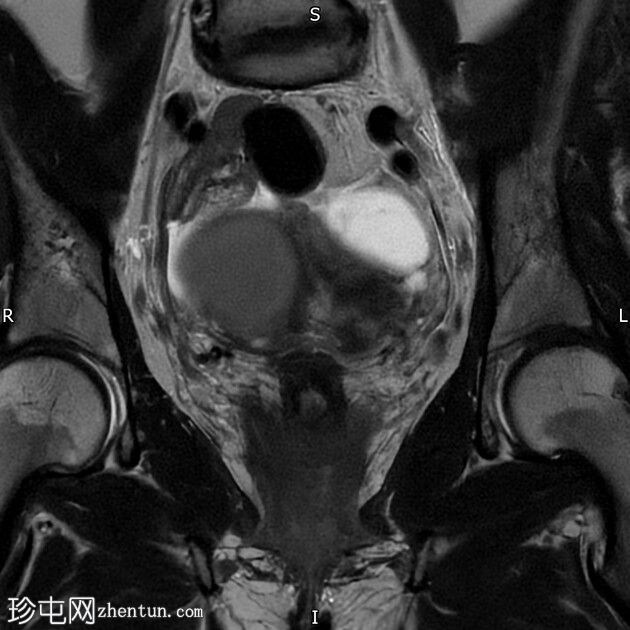

轴位T1加权像

脂肪抑制像

右侧卵巢囊肿,T2加权像呈低信号,T1脂肪抑制像呈高信号,大小为6 x 5.2 cm,符合子宫内膜异位囊肿的影像学表现。

左侧卵巢囊肿,T2加权像呈低信号,T1脂肪抑制像呈高信号,符合子宫内膜异位囊肿的影像学表现。

双侧卵巢粘连于后道格拉斯窝,呈“接吻卵巢征”。